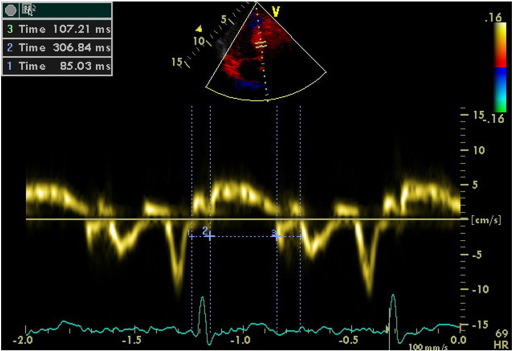

2.2. Pulsed tissue doppler imaging

Tissue Doppler Imaging (TDI) permits a quantitative assessment of both global and regional function and timing of myocardial velocities. Pulsed TDI was performed at transducer frequencies of 3.5-4.0 MHz, adjusting spectral Doppler filters until a Nyquist limit of 15-20 cm/s was reached, and using minimal adequate gain. TDI was performed using LV apical 4-chamber imaging and sample volume was subsequently placed on the basal septal (Fig. 1) and basal lateral segment walls in the apical four-chamber view. It is documented that the basal region is associated with the greatest and the most reliable tissue velocity compared with other regions [10]. The imaging angle was adjusted to ensure a parallel alignment of the sampling window with the myocardial segment of interest. Color noise reduction was adjusted, and a color Doppler scanning frame rate of 100 to 140 Hz was used. Myocardial E’ and A’ waves were obtained from LV septal wall, than E/E’ was calculated. Isovolumetric contraction time (IVCT), contraction time (CT), and isovolumetric relaxation time (IVRT) were measured and myocardial performance index (MPI) calculated from the base of septal and lateral walls using the Tei Index which was shown to be valuable in hypertensives [11].

Evaluation of isovolumetric contraction time, contraction time and isovolumetric ...

Fig. 1.

Evaluation of isovolumetric contraction time, contraction time and isovolumetric relaxation time of the LV septal base by tissue Doppler imaging in a hypertensive patient (MPI = 51).